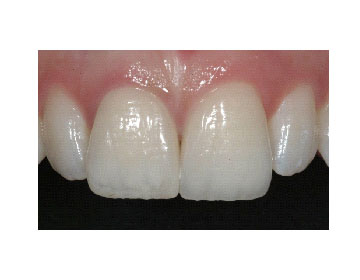

Oggi tutto questo è finalmente possibile grazie allo sviluppo di nuove tecnologie che offrono a tutti l'opportunità di risolvere in poco tempo in maniera efficace, sicura e predicibile problemi funzionali ed estetici che prima richiedevano molte sedute operative e un notevole impegno da parte del paziente. Oltre allo sbiancamento con luce al plasma, è il computer ad avere assunto un ruolo fondamentale nella realizzazione di restauri mini-invasivi come le faccette e le corone "senza metallo". Il computer prima disegna le protesi e successivamente le realizza fresando materiali bio-estetici di ultima generazione come l'allumina e la zirconia. Una corona ed una faccetta in ceramica integrale.